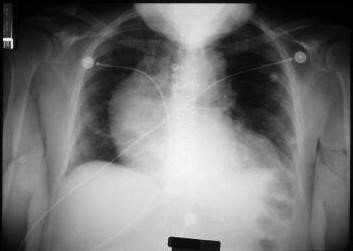

- Döş qəfəsinin Rentgenoqrafiyası, EKQ;